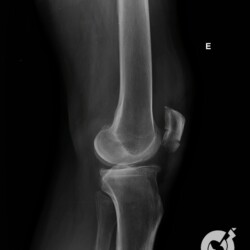

Fratura da patela com importante desvio e fratura cominutiva do 1/3 proximal da tíbia comprometendo a eminência intercondiliana.